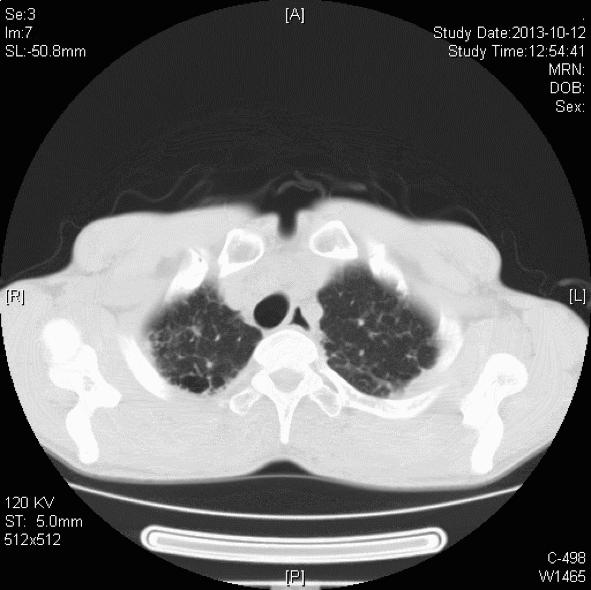

胸部CT:双肺胸膜下见斑片状磨玻璃影、模糊小结节灶及纤维网格状影,似乎和我们常见的肺纤维化IPF不太一样,以双上肺为主。右下肺外基底段片状影,边界模糊,局部支气管略显增宽(本院,2013-10-12)。